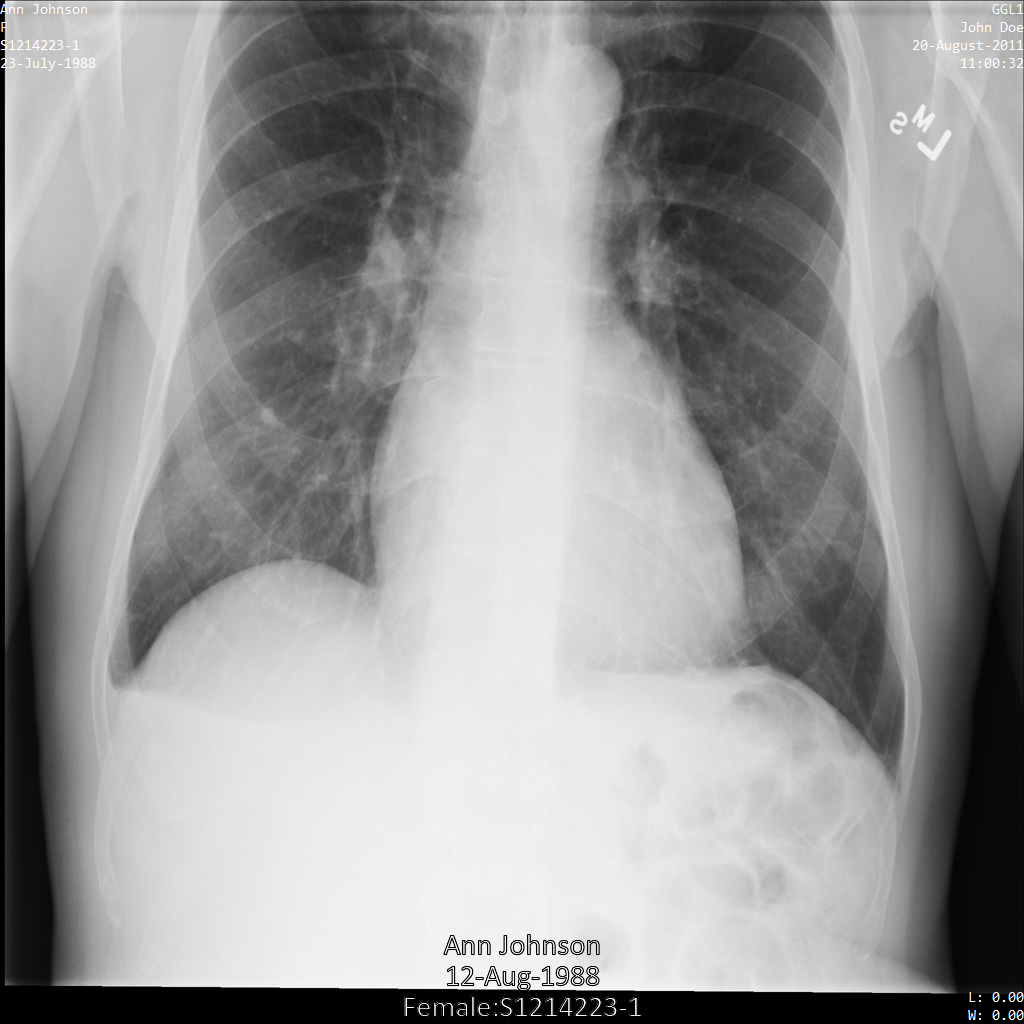

Nachdem Sie das Image an die Cloud Healthcare API gesendet haben, wird es wie folgt angezeigt. Von den in der Entfernungsliste angegebenen Tags wird nur PatientBirthDate aus dem Bild entfernt, da es das einzige Tag aus der Entfernungsliste ist, das den Metadaten entspricht, die im Bild sichtbar sind.

Während das PatientBirthDate in der oberen Ecke des Bildes gemäß der Konfiguration in der Entfernungsliste entfernt wurde, bleibt die eingebrannte PHI unten im Bild erhalten. Informationen zum Entfernen des eingebrannten Texts finden Sie unter Eingebrannten Text aus Bildern entfernen.